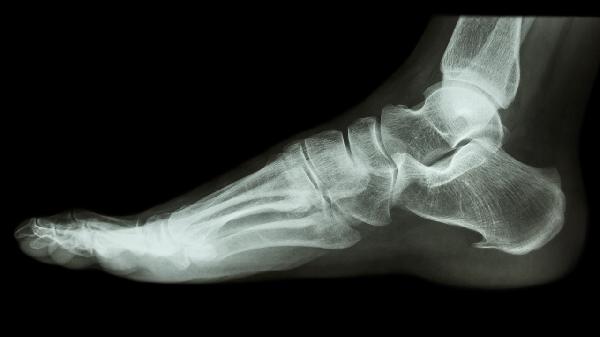

第四脚趾骨折不固定能否自愈需根据骨折类型决定,轻微裂缝性骨折可能自愈,但移位性骨折通常需要固定治疗。第四脚趾骨折多由外伤、挤压或长期劳损引起,建议及时就医评估。

裂缝性骨折表现为局部肿胀、轻微疼痛,但脚趾形态和功能基本正常。此类骨折可通过限制活动、穿戴硬底鞋保护,促进骨骼自然愈合。恢复期间避免负重行走,适当抬高患肢有助于消肿。若疼痛明显,可遵医嘱使用布洛芬缓释胶囊、对乙酰氨基酚片等药物缓解症状。

移位性骨折会出现明显畸形、异常活动或持续性剧痛。此时不固定可能导致骨骼错位愈合,影响行走功能。需通过手法复位后采用夹板、石膏或手术钢钉固定。严重者可能需使用接骨七厘片、伤科接骨片等促进骨痂形成,配合康复训练恢复关节活动度。

骨折后应保持足部清洁干燥,避免感染风险。饮食需增加牛奶、鱼肉等富含钙质和优质蛋白的食物,戒烟戒酒以防影响愈合。定期复查X光片监测愈合进度,若出现皮肤发紫、剧烈疼痛或发热需立即就医。未经专业评估自行处理可能延误治疗,导致慢性疼痛或关节炎等后遗症。